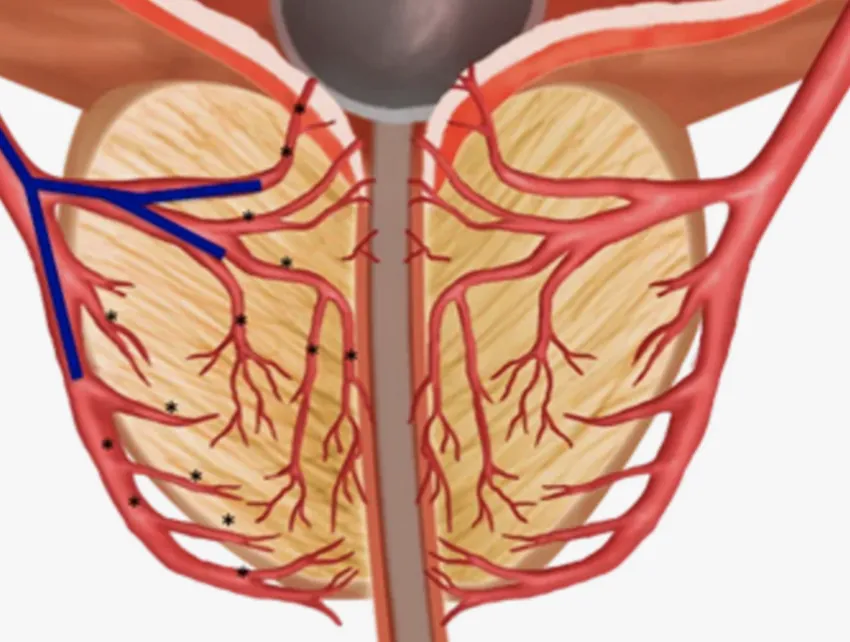

Справа в тому, що передміхурова залоза має складну систему кровообігу. І саме через її погіршення залоза стає слабкою, у неї знижуються імунні властивості і в ній заводяться хвороботворні бактерії. Тобто розвивається бактеріальний простатит.

Передміхурова залоза має

складну систему кровообігу

Передміхурова залоза має

складну систему кровообігу